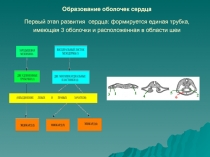

- Медицина